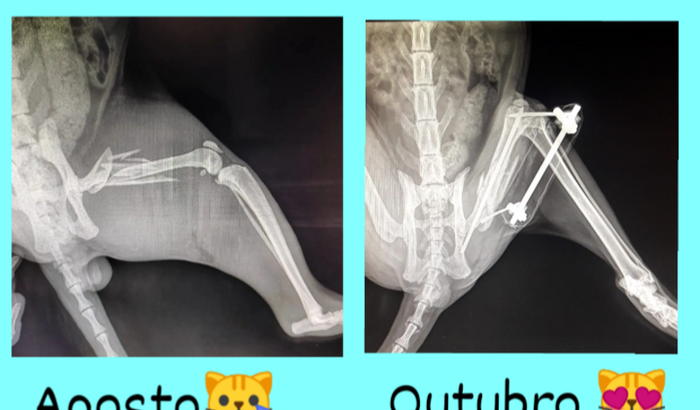

***Atualizando***  O gatão Júpiter tirou os pinos hoje dia 01/11 e vai poder caminhar tranquilamente! 💙     ver tudo

***Atualizando***  O gatão Júpiter tirou os pinos hoje dia 01/11 e vai poder caminhar tranquilamente! 💙